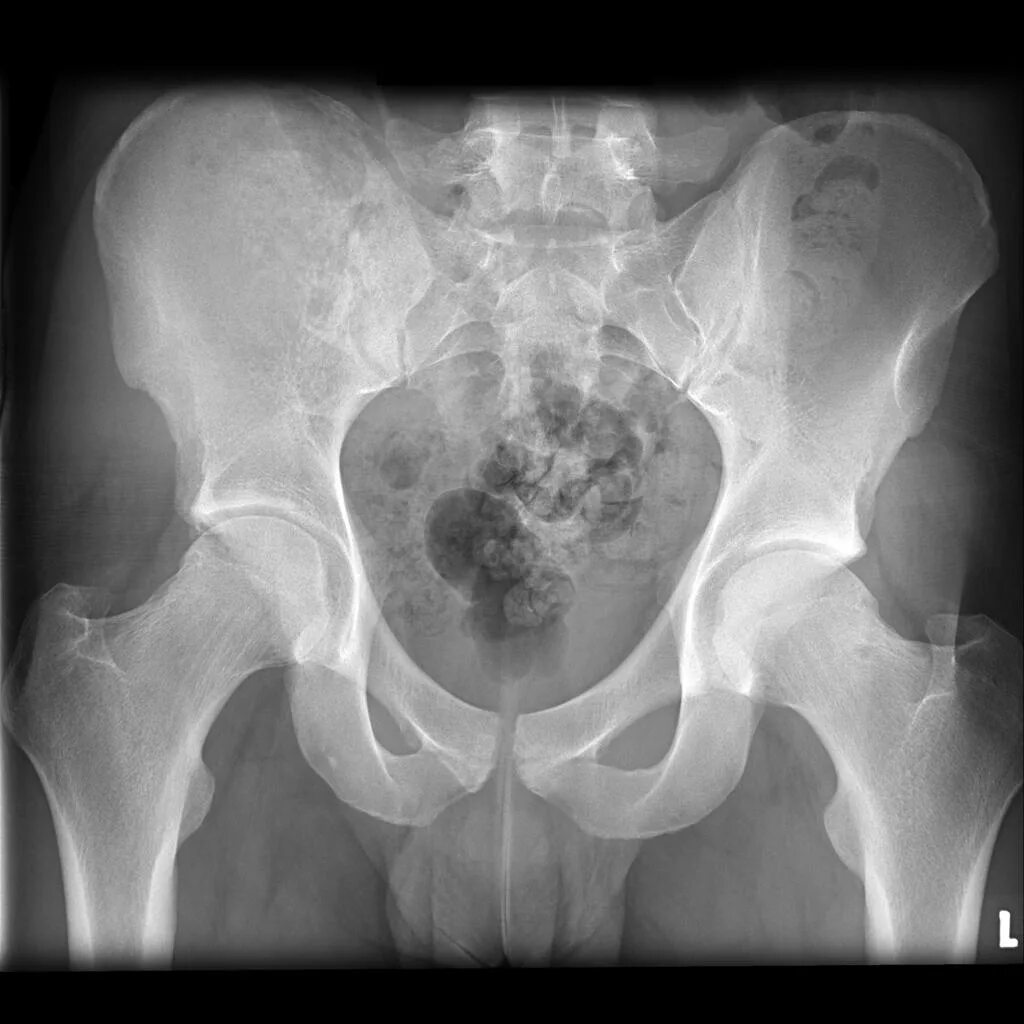

Метастазы в крестце